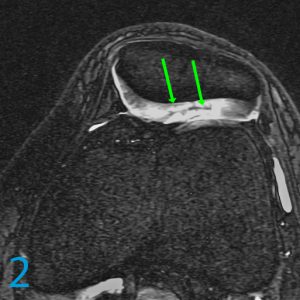

5. What adjectives might you use to describe the abnormality highlighted by the green arrows on image 2?

5. Intrasubstance delamination and intrasubstance separation of the middle layer of lateral patellar facet cartilage.